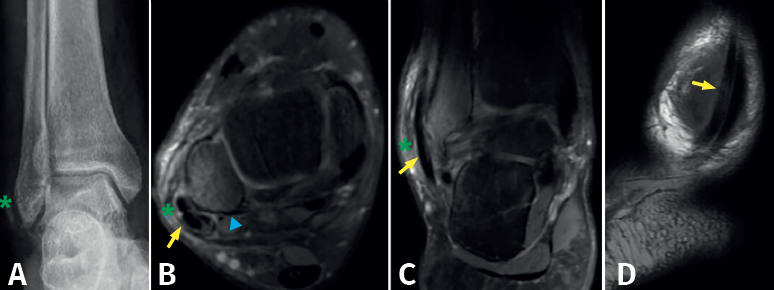

Tras 7 meses de evolución, el paciente es derivado por el Servicio de Rehabilitación por primera vez a consultas externas de traumatología, por persistencia del dolor, limitación funcional y mala evolución del “esguince”. Precisa de 2 muletas, limitación completa de la flexoextensión y eversión del pie. Revisando la radiografía inicial del tobillo derecho (Figura 1A) realizada en urgencias, se observa una fractura-arrancamiento de la cortical externa del maléolo peroneo (fleck sign o signo de la mancha, que indica lesión del RPS). La resonancia magnética (RM) del tobillo derecho, solicitada por el Servicio de Rehabilitación, informa de “avulsión de cortical externa, edema óseo, sinovitis y tendinitis de tendones peroneos”, pero revisando las imágenes de la RM (Figuras 1B a 1D) en nuestra consulta, se observa luxación evidente de los tendones peroneos.

Nuestro paciente presentaba un surco convexo (Figura 1B) y una luxación de los tendones peroneos de grado III de Eckert y Davis crónica, con avulsión ósea del RPS en el maléolo. Ante estos hallazgos, con un fragmento avulsionado de cortical lateral del maléolo peroneo en pseudoartrosis, decidimos, además de profundizar el surco retromaleolar y reparar el RPS mediante la reinserción del fragmento cortical avulsionado, realizar una técnica de bloque óseo con el objetivo de aportar mayor estabilidad a los tendones peroneos. Se trata de un caso de luxación crónica de los tendones peroneos tratado con técnica de bloque óseo que aporta un resultado clínico satisfactorio y sin complicaciones.